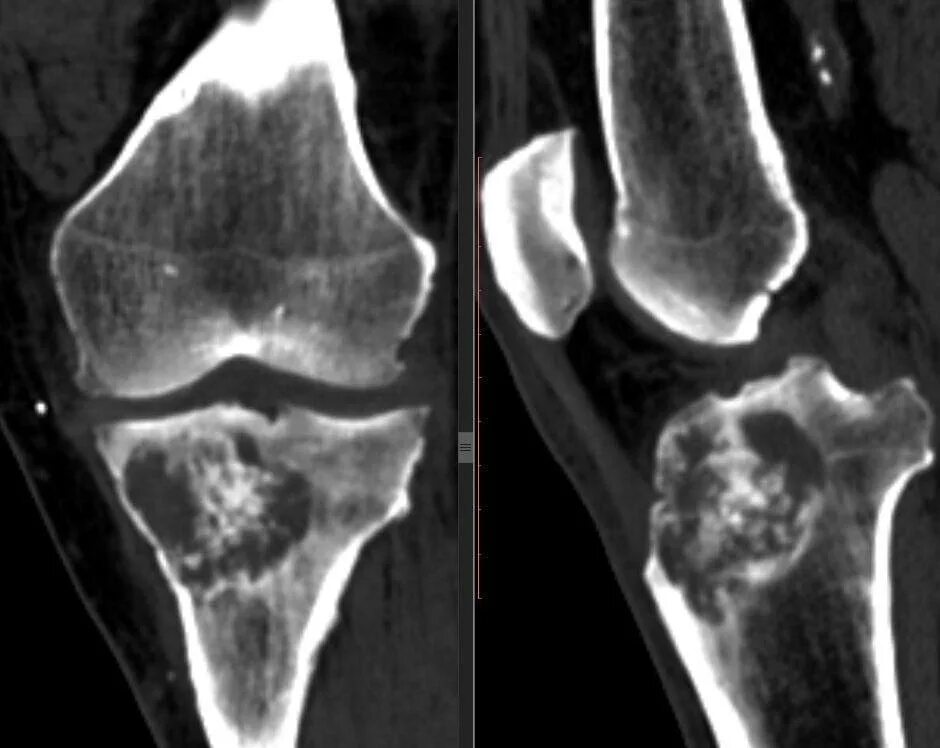

Гонартроз мрт